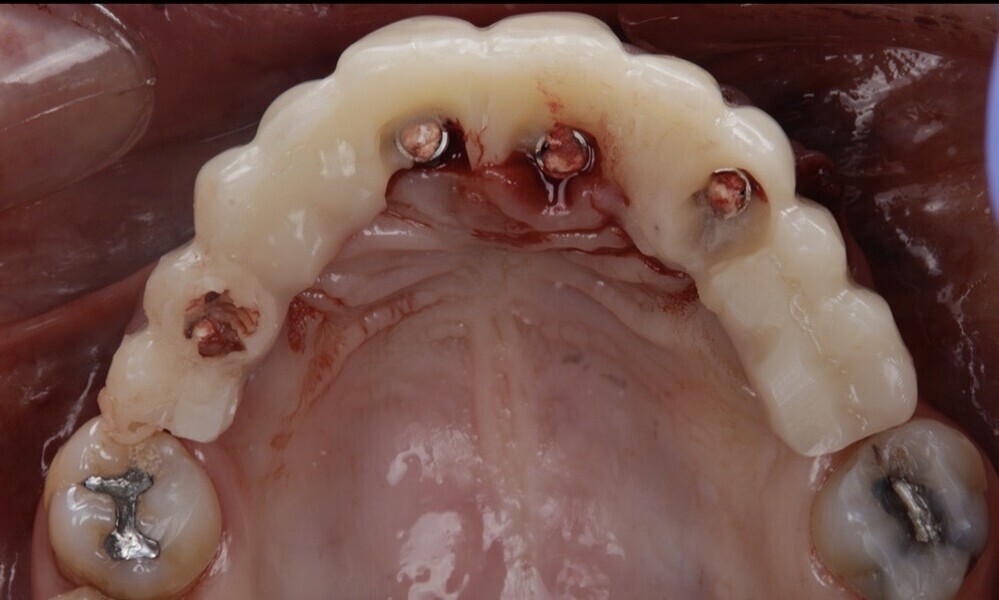

Temporary abutments were then placed on top of the screw-retained abutments to ensure stability and support of the provisional restoration (Figs. 61 & 62). The provisional restoration was carefully tightened to between 15 N cm and 35 N cm on the temporary abutments directly in the mouth to ensure a precise fit, optimal comfort and proper functionality for the patient (Figs. 63–66).

Figs. 61 & 62: Temporary abutments were placed on top of the screw- retained abutments.

Figs. 63–66: The provisional restoration was secured to the temporary abutments.